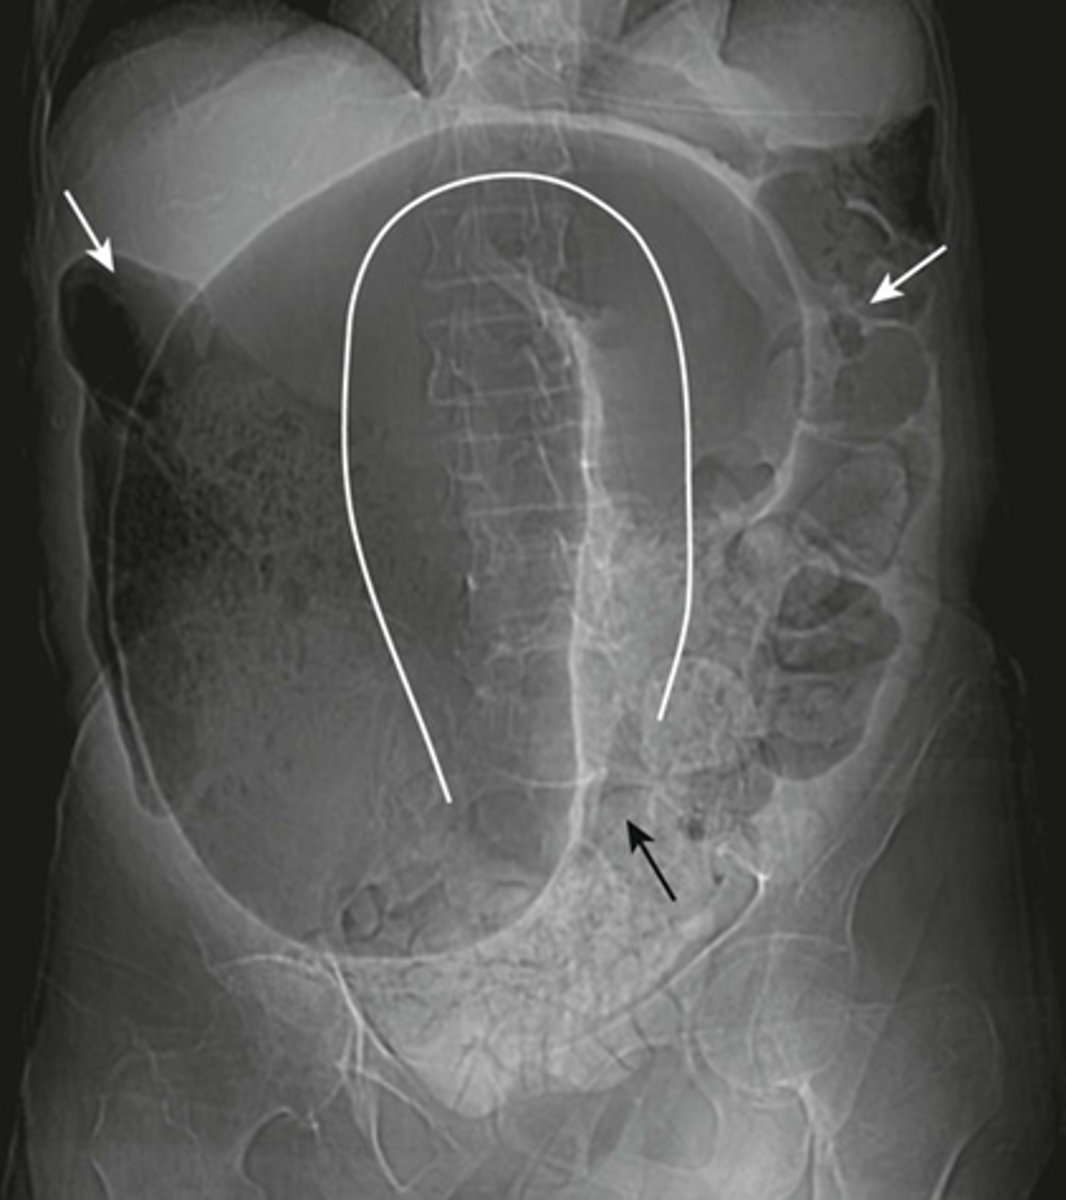

Volvulus

SOLID WHITE LINE:

massively dilated sigmoid colon, twisted upon itself in the pelvis

BLACK ARROW:

pelvis

WHITE ARROW:

more proximal portion of the colon filled with air and stool.